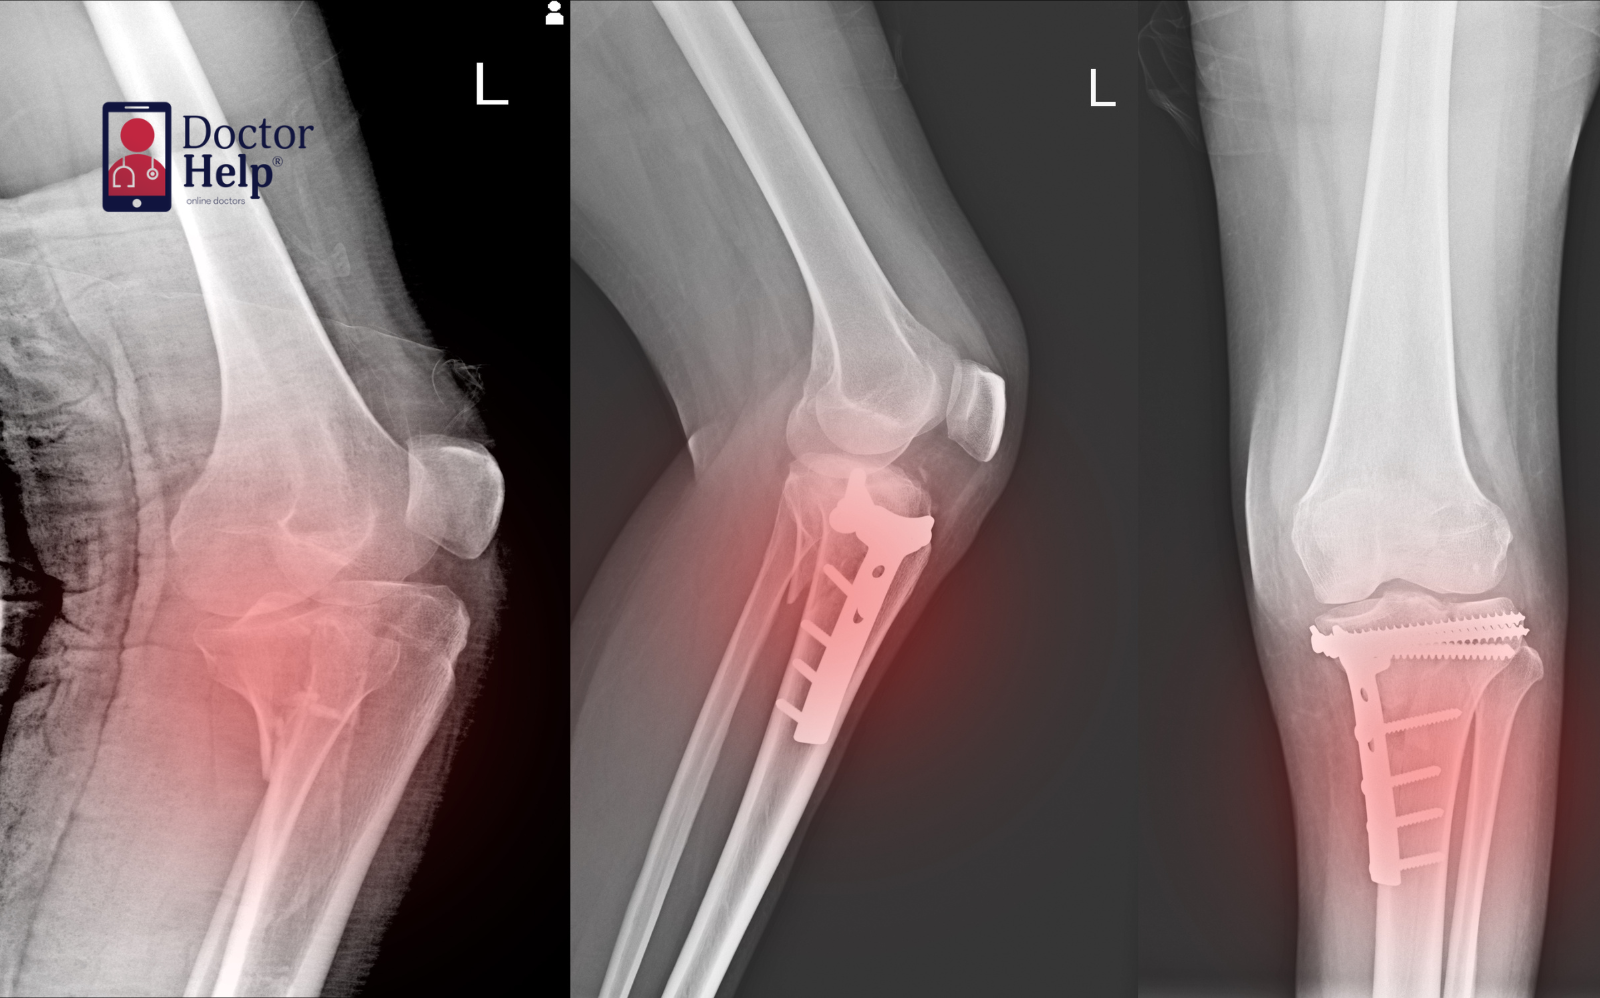

Fractures & stress fractures – bone injuries requiring recovery planning

- Frequent fractures or stress fractures